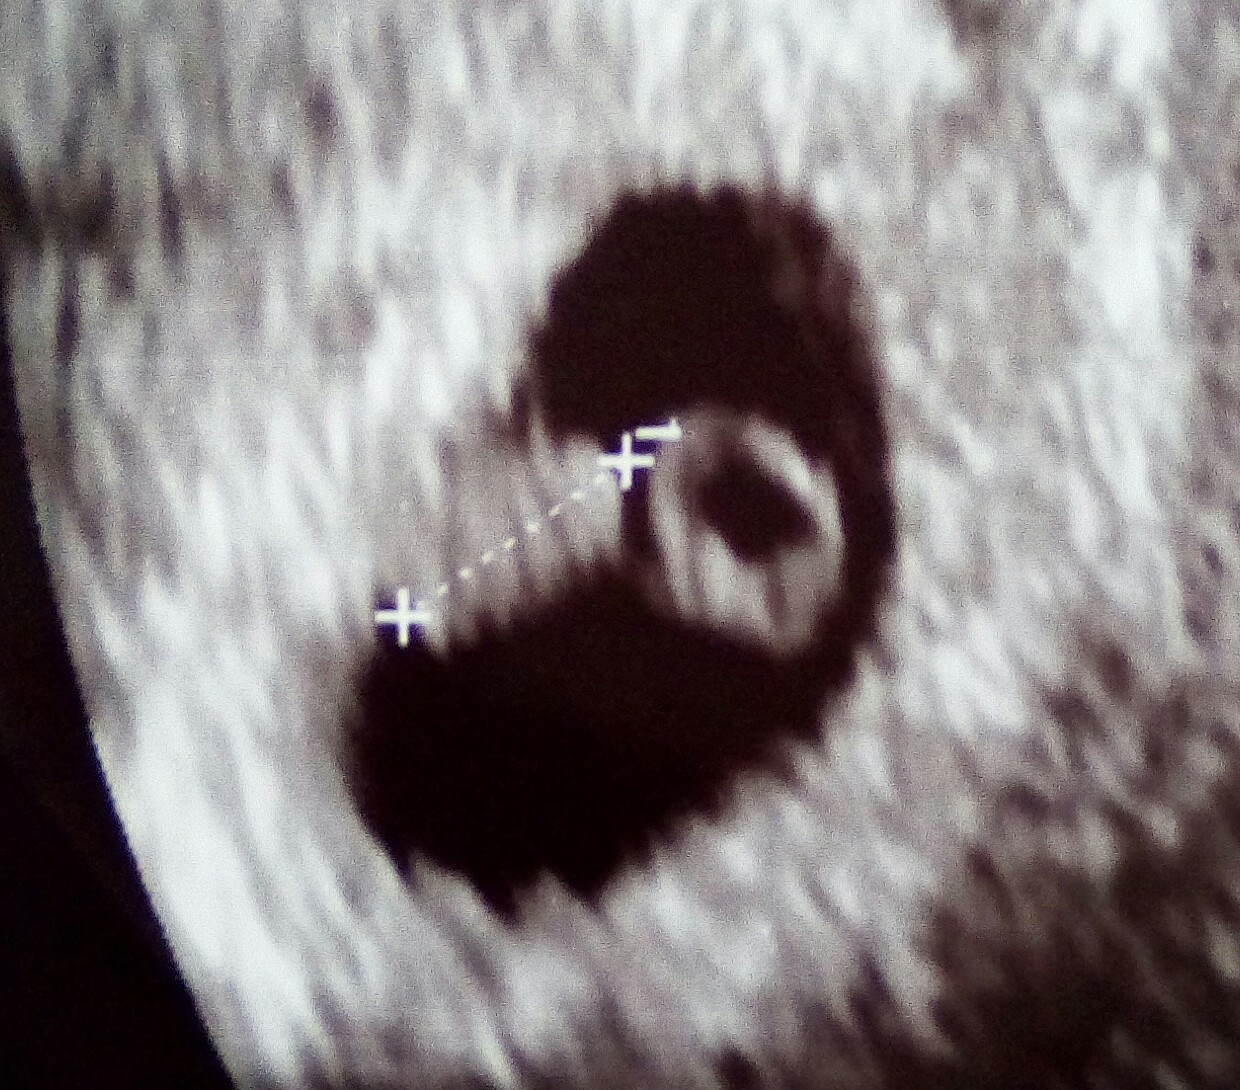

Jeszcze żeby wysłać pozytywną energię dorzucam zdjęcie z usg tego dużego maluszka przybliżone bo niestety za duży rozmiar był :-) :)oby coraz

IMG_20170619_203212_431.JPG

więcej takich zdjęć tutaj było

Jeszcze żeby wysłać pozytywną energię dorzucam zdjęcie z usg tego dużego maluszka przybliżone bo niestety za duży rozmiar był :-) :)oby corazZobacz załącznik 811451 więcej takich zdjęć tutaj było